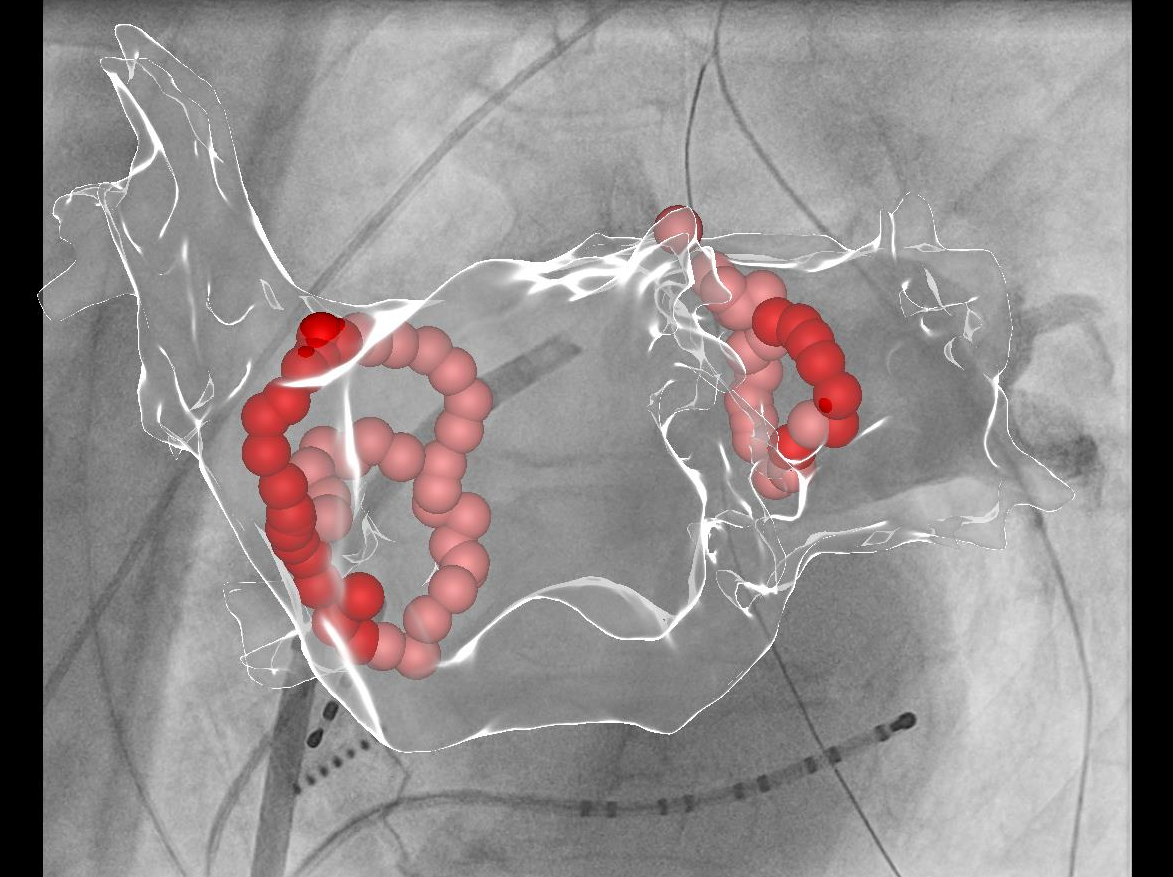

Vorhofflimmer Therapie - persönlich und individualisiert

Vorhofflimmern ist mit Abstand die häufigste Rhythmusstörung - jeder 3. Europäer wird im Laufe seines Lebens daran erkranken. Erfahren Sie mehr, wie wir Vorhofflimmern mit modernster Kathetertechnik behandeln - egal, ob Sie seit kurzem erkrankt sind, oder die Erkrankung bereits chronifiziert ist. Wir finden für Sie die richtige Technologie!